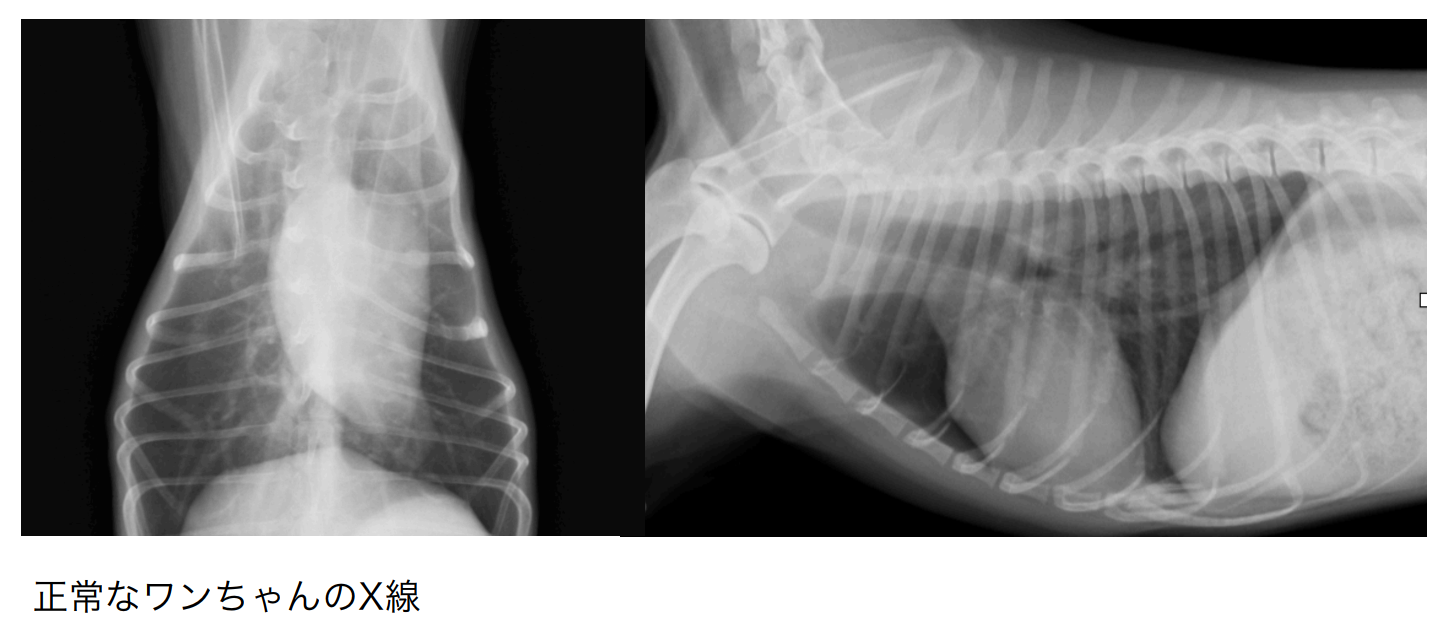

犬の心臓病 僧帽弁閉鎖不全症 その3

前回に引き続き、僧帽弁閉鎖不全症という心臓病のお話になります。

前回は症状がない状況の僧帽弁閉鎖不全症の話でしたが、今回はいよいよ深刻な症状…命に関わる症状の話となります。